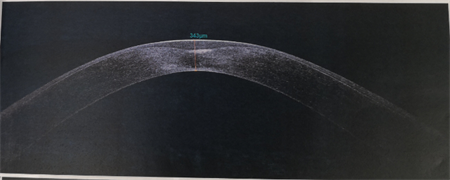

商旭敏副主任告訴我們,小蕓的右眼已經(jīng)是圓錐角膜后期,角膜厚度僅有343,再繼續(xù)發(fā)展下去,就會水腫破裂。由于圓錐角膜都是雙眼發(fā)病,小蕓的左眼此時(shí)也開始出現(xiàn)圓錐角膜的癥狀了。

▲小蕓右眼厚度343,左眼厚度523